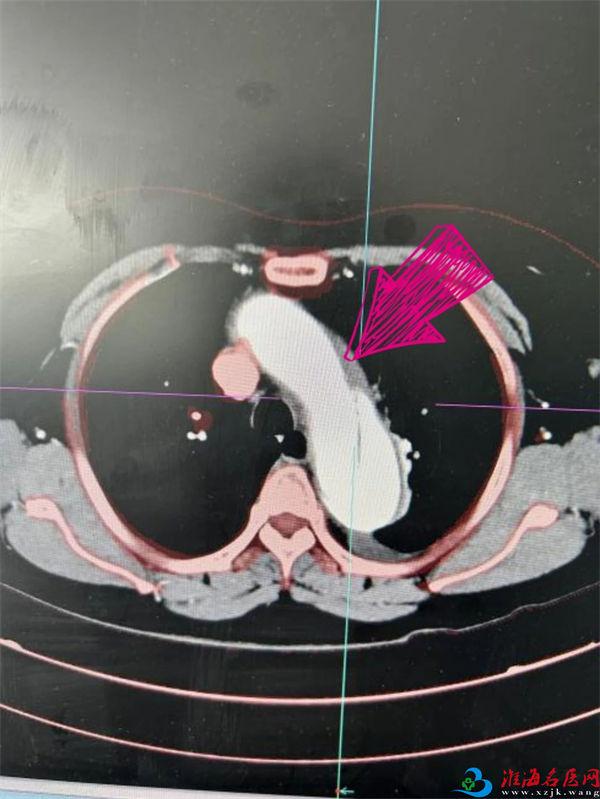

W女士10天前劳累后突发腹部撕裂样疼痛,伴后腰背部放射痛,无恶心呕吐,无寒战高热,就诊于当地医院予以对症治疗,症状未见明显改善,慕名到徐州一院就诊。入院后立即完善相关检查,胸腹主动脉CTA结果令人揪心:胸主动脉夹层(B型)——这意味着患者的血管壁已因长期高血压冲击变得脆弱不堪,犹如一根布满裂痕的“老化水管”,随时可能崩裂。

术  前

术  后

与此同时,在介入导管室护士长孙宁及其团队护理骨干张琨、赵康和技师郑红云的默契配合下,薛松教授团队骨干、上海仁济医院心血管外科副主任医师刘冀东,徐州一院心脏大血管外科执行主任、医学博士单江桂和副主任医师王峦通力协作,精准定位夹层破口,在DSA引导下将覆膜支架精准送至夹层破口处。随着支架成功释放、假腔血流消失,手术顺利结束。